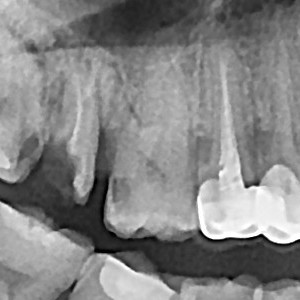

충치치료&신경치료 하루에 끝나는 신경치료

ab84f1a97a55df0651436bf31adcdd0f_1767396700_1373.jpg